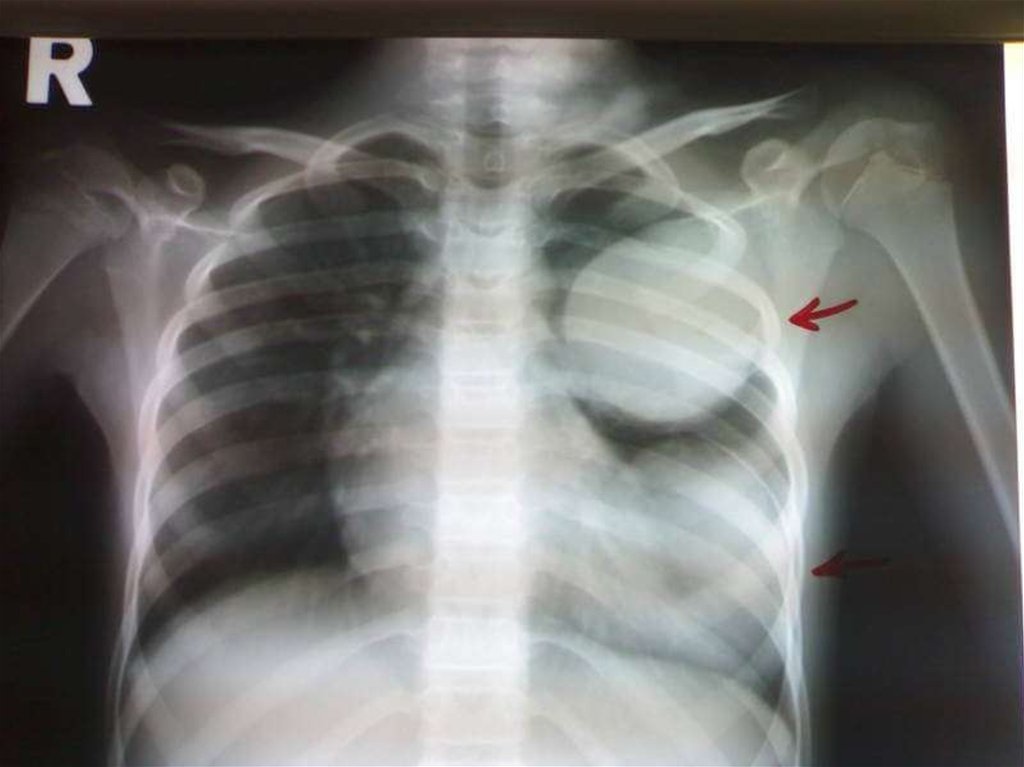

Если поражены легкие, клинические признаки

включают хронический кашель, боли в груди и

нехватку дыхания